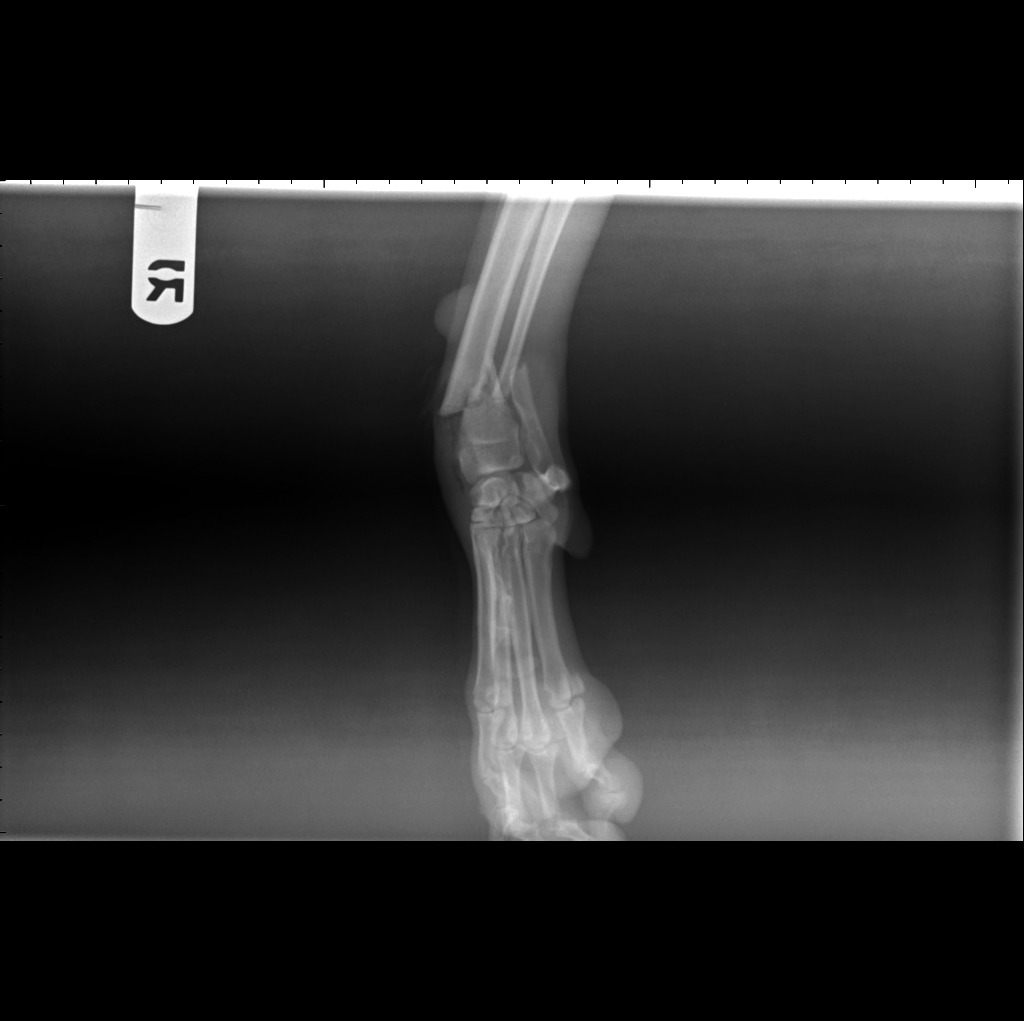

On November 28th, at about 12:40 pm, my baby Elsa was hit by a car that fled the scene. She is suffering from a completely broken right leg, fractured and bruised ribs, and bruising on her liver. Elsa now urgently needs a 3-hour surgery by a bone specialist, along with follow-up care so she can return to her original quality of life.